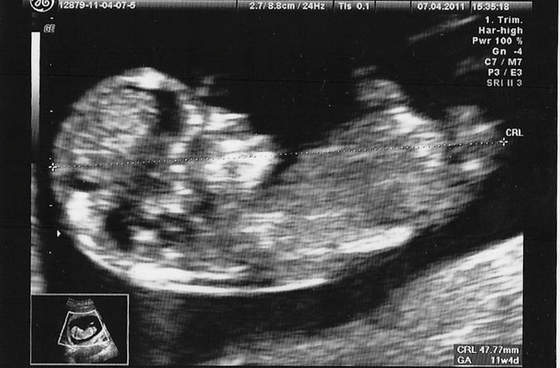

Tak wyglądał mój synek w 12tc.

A tak wyglądają dzidziusie na normalnym usg w tym tygodniu